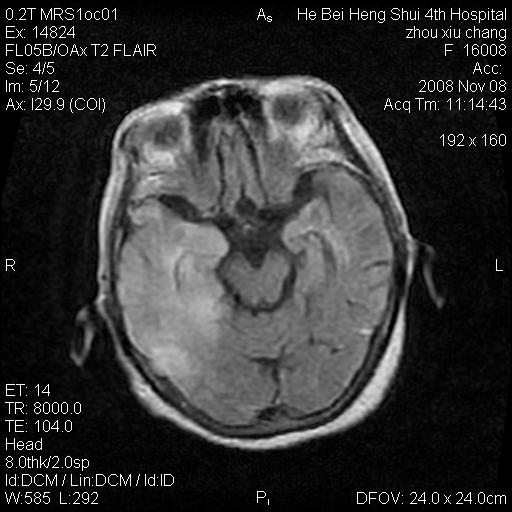

标题: MRI1883:女67岁,半年前曾患脑梗塞,治疗后好转,近3各月精

女67岁,半年前曾患脑梗塞,治疗后好转,近3各月精神恍惚。

形态及整体病灶看起来首先考虑转移瘤或淋巴瘤,但奇怪的是多个病灶周围均未见显著的水肿区,这不符合这两个肿瘤的特点,结合ct表现及患者病史有个人考虑是否有皮层下动脉硬化性脑病伴多发胶质增生可能.